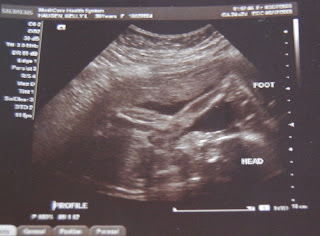

More pics of Miss Thing

This morning I was laying in bed trying to talk myself into getting up when Miss Thing decided that she was going to be up too. I had my hand/arm slung across my stomach when all of a sudden it must have been bothering Miss Thing as she gave it a big boot and my hand/arm jumped off my stomach. It was so funny. I laid it back down in the same place and she continued to kick the crap out of it. Apparently it was in her way or her space or whatever. For some reason she had an issue with it being there. Oh the attitude at such a young age:/